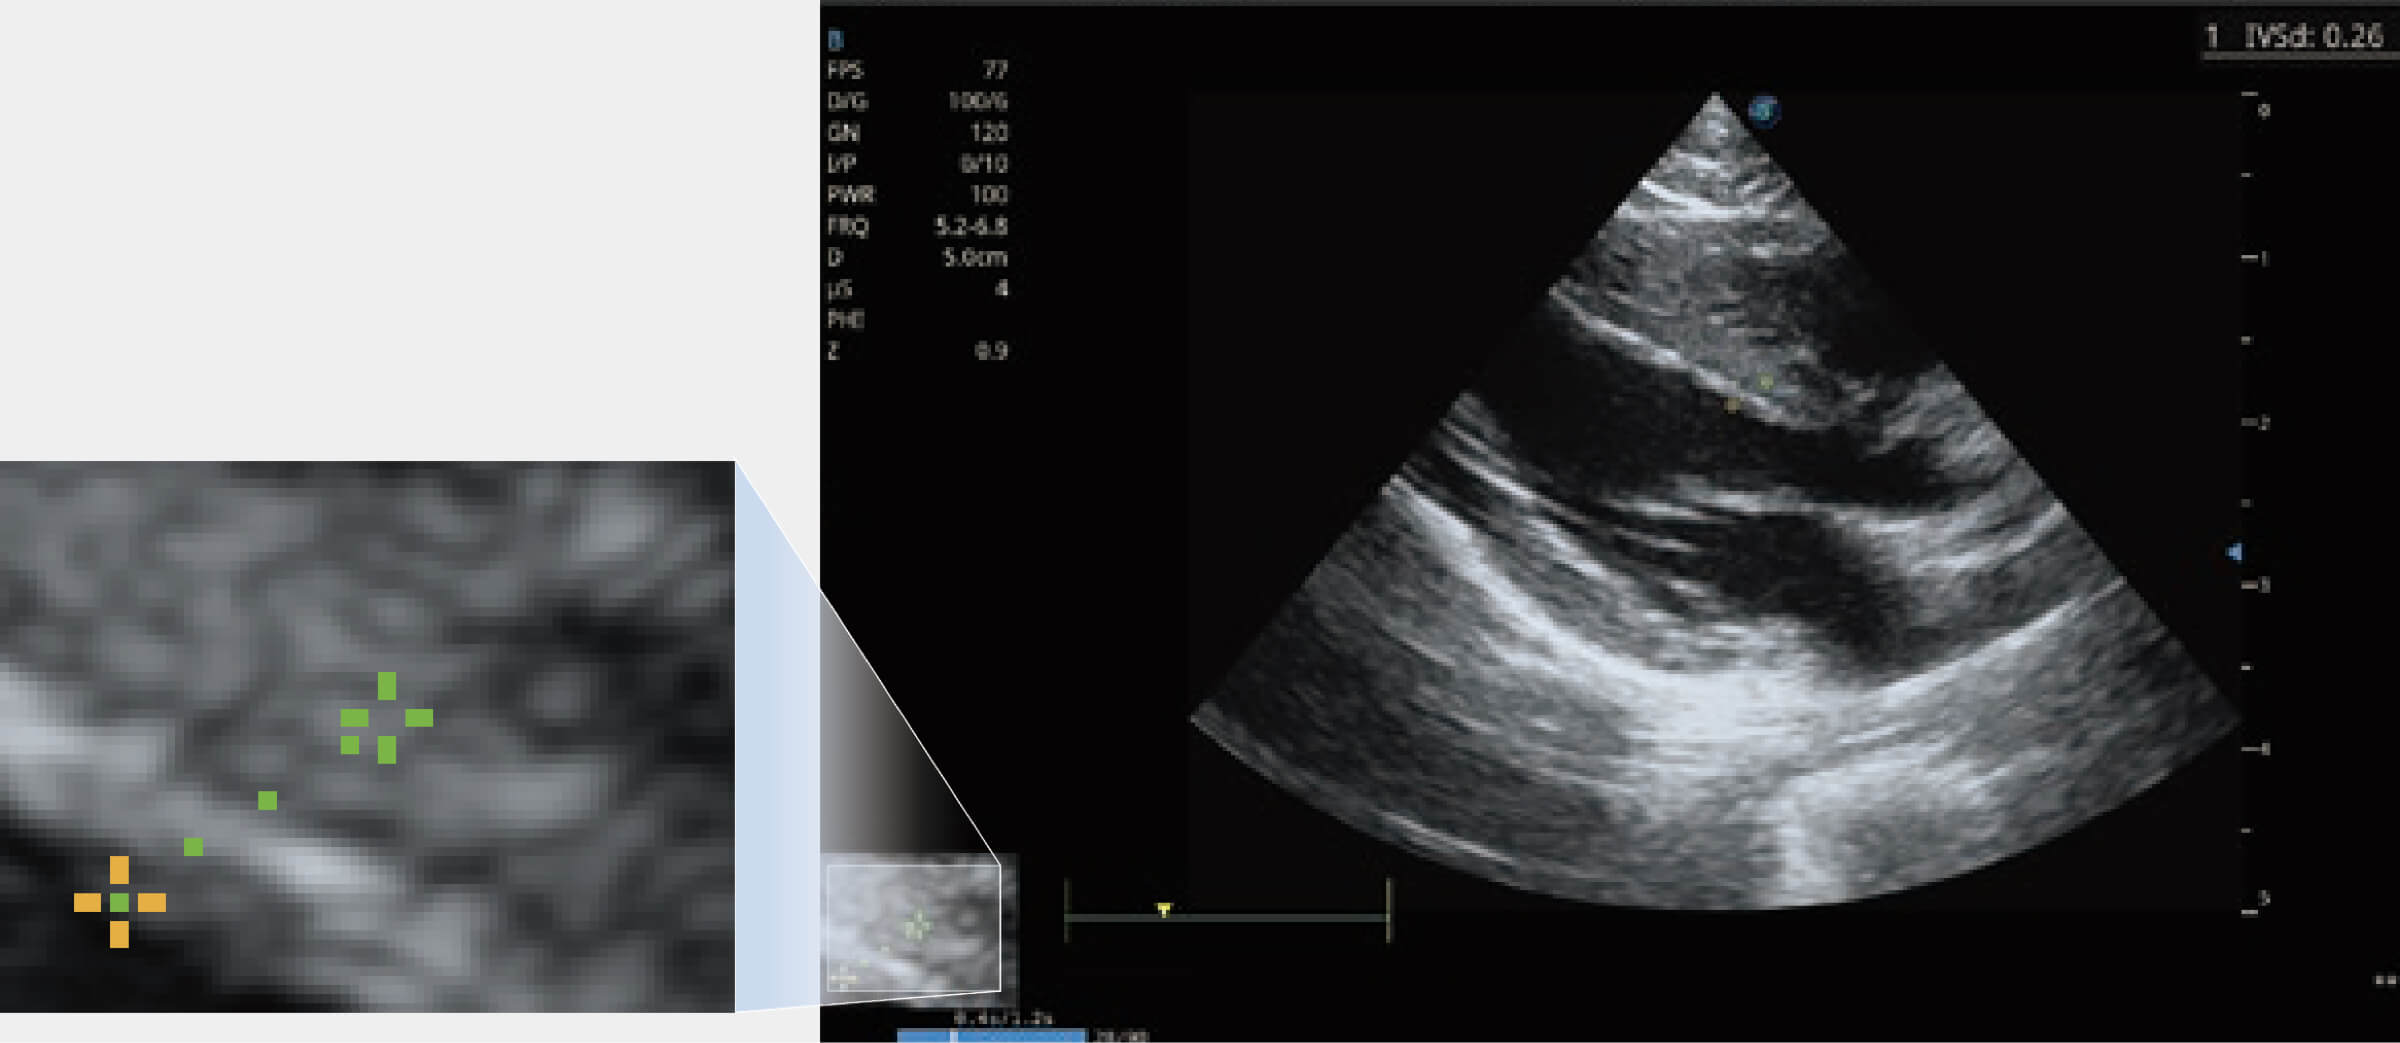

ProPet 70 進(jìn)一步提升了微米成像算法,更加注重對基礎(chǔ)原始圖像的還原和保留,在有效減少斑點(diǎn)噪聲、增強(qiáng)組織邊界顯示的同時(shí),避免過度優(yōu)化丟失真實(shí)的解剖信息。

通過360度任意調(diào)節(jié)3條M型取樣線,在同一心動周期上觀察心臟不同位置的運(yùn)動曲線,得到準(zhǔn)確的心功能測量數(shù)據(jù),有效評估心肌運(yùn)動及左心室功能。

當(dāng)心臟測量結(jié)果超出正常范圍時(shí),可實(shí)時(shí)預(yù)警提示動物醫(yī)生,減少疾病漏診概率。